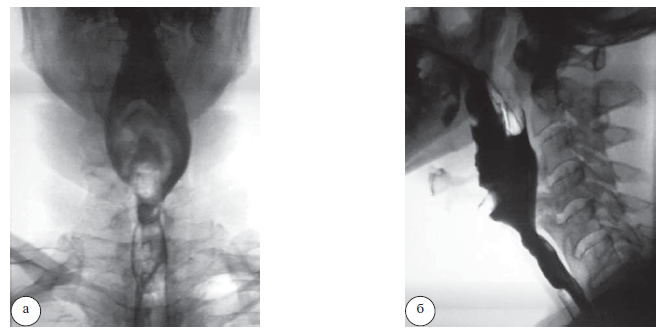

Под общей многокомпонентной интубационной анестезией выполнено микрохирургическое удаление очагов гиперостоза CIII и СIV позвонков и декомпрессия гортани и глотки передним доступом. Длительность операции составила 85 мин, кровопотеря – менее10 мл. Послеоперационный период протекал без осложнений. Дисфагия и дисфония полностью регрессировали через 8 дней после операции. Сохранялась эпизодическая умеренная ноющая боль в области операции. Пациент неоднократно посещал контрольные осмотры вплоть до 2010 г. Отмечалась положительная динамика, и до 2018 г. болезнь не беспокоила пациента. В конце 2018 г. пациент отметил возобновление болевого синдрома в шее и осиплости голоса. Больной был проконсультирован оперировавшим нейрохирургом, который диагностировал рецидив болезни Форестье на ранее оперированном уровне. Диагноз был подтвержден данными КТ и МРТ шейного отдела позвоночника – максимальная выраженность гиперостоза была на уровне СIII–CV позвонков (рис. 1).

Рис. 1. Предоперационные данные КТ (а, б) и МРТ (в, г) шейного отдела позвоночника. Гиперостоз передней продольной связки на уровне СIII, CIV и СV позвонков (указан стрелками)

В течение 3 месяцев пациент лечился консервативно НПВС, но положительного эффекта не было, напротив, симптоматика прогрессировала, и присоединилась невозможность глотания твердой пищи. При рентгеноскопии глотки и пищевода с барием отмечена задержка прохождения контрастного вещества на уровне CIV и СV позвонков (рис. 2).

Рис. 2. Рентгеноскопия глотки и пищевода с барием в боковой (а) и прямой (б) проекциях. Задержка прохождения контрастного вещества на уровне CIV и СV позвонков